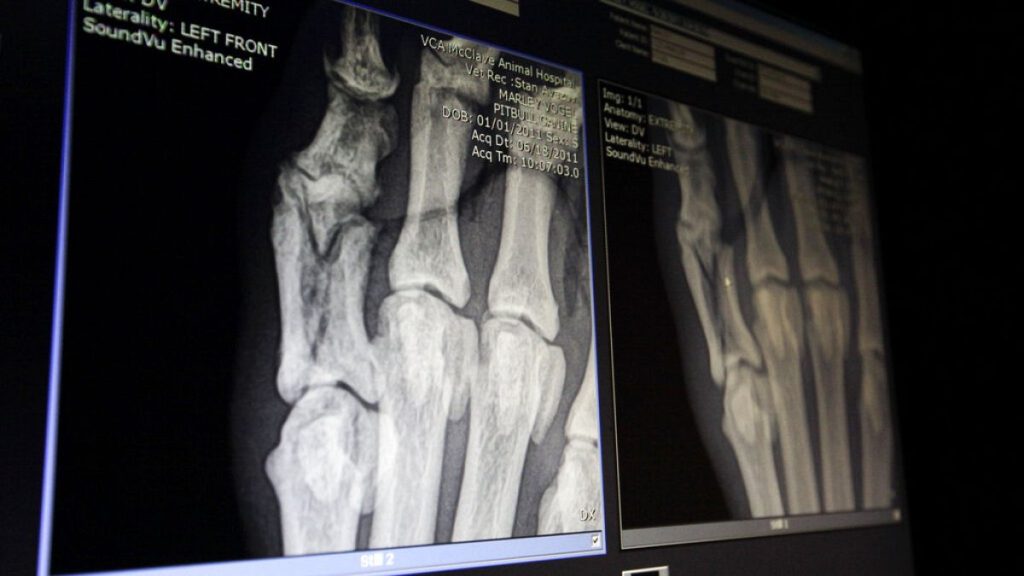

وفي التجارب الحيوية، استُخدم الزجاج الحيوي الجديد لإصلاح عيوب في عظام جمجمة الأرانب، إلى جانب عيّنات من زجاج سيليكا عادي مطبوع ثلاثي الأبعاد، وبدائل عظمية تجارية شائعة.

وأظهرت النتائج أن البديل التجاري حقّق نموًّا عظميًّا أسرع في المراحل المبكرة، لكن الزجاج الحيوي استمر في دعم تكوين الخلايا العظمية على المدى الطويل؛ فبعد 8 أسابيع، غطّت الخلايا العظمية معظم سطح سقالته، بينما سجّل الزجاج العادي نموًّا ضئيلًا جدًّا.